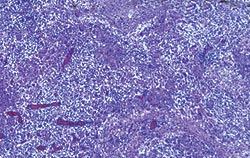

| Quantité modérée | |

| Faible quantité | Quantité élevée |

Quantités faible, modérée et élevée de génome de PCV2 dans les organes lymphoïdes. Les deux images de droite correspondent à des cas de MAP. Technique d’hybridation in situ.